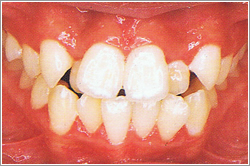

上下の前歯がでこぼこに並んでいます。

典型的な例は八重歯。